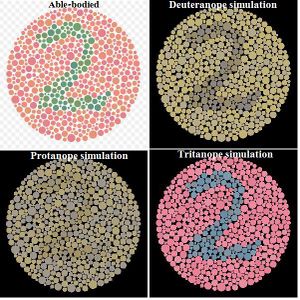

This image contains the number 37, but someone who is protanopic may not be able to see it.

This image shows a number 49, but someone who is deuteranopic may not be able to see it.